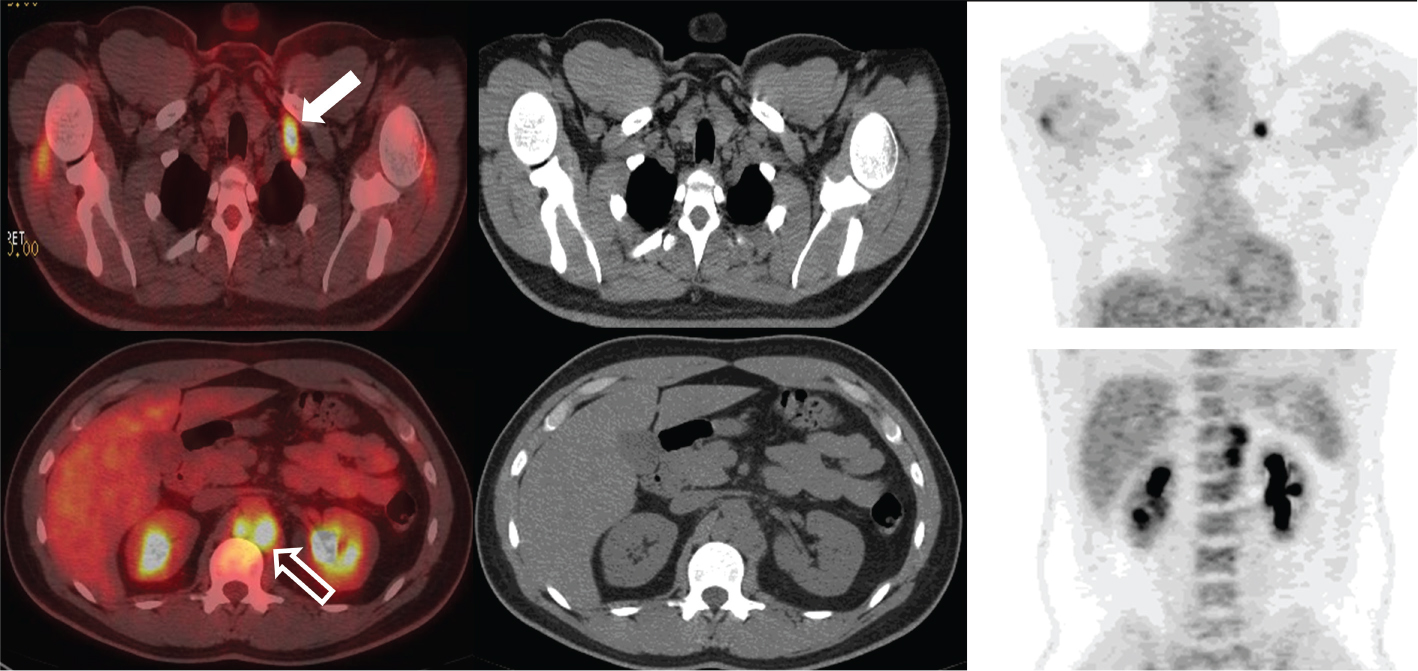

Fig 2

Figure 2. Penile base, surgical site, and lymph nodes. FDG PET/CT demonstrates hypermetabolic activity within the penile base (thick solid arrow), surgical site (thick open arrow), and bilateral inguinal lymph nodes (thin arrows). This patient was status post partial penectomy and chemotherapy for penile squamous cell carcinoma. Findings on PET/CT were consistent with progression of disease and poor response to chemotherapy.